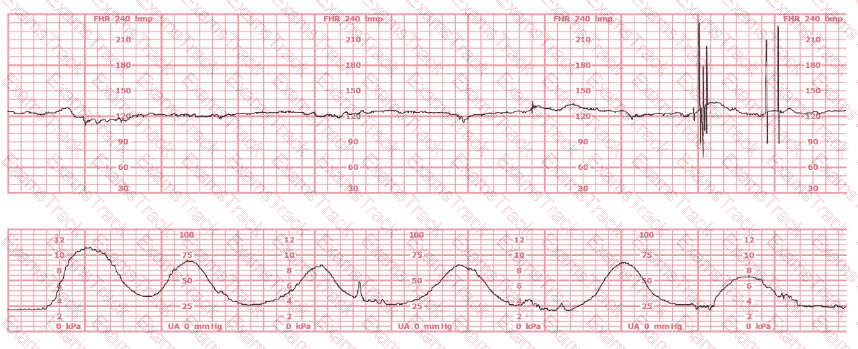

The fetal heart rate baseline is approximately 150 bpm, which is within the normal range of 110–160 bpm.

The tracing shows minimal variability (approximately 1–4 bpm amplitude). Minimal variability for a sustained period is categorized as a Category II pattern under NCC/NICHD classification.

No accelerations are present during the 20-minute representative segment.

There are no recurrent variable, no recurrent late, and no prolonged decelerations.

The tracing shows very frequent contractions—approximately every 1½ to 2 minutes, which meets the NCC definition of tachysystole when averaged over 10 minutes (more than 5 contractions in 10 minutes).

According to NCC and AWHONN standards, when tachysystole is present with minimal variability, oxytocin must be reduced or discontinued even in the absence of late decelerations.

NCC emphasizes that management of Category II patterns during induction starts with intrauterine resuscitative measures, including decreasing or stopping oxytocin when uterine activity is excessive or fetal response is suboptimal. Minimal variability with tachysystole requires correction of uterine stimulation before escalating to invasive monitoring or considering operative birth.

Option A (discontinue oxytocin) is the correct first-line action according to NCC-aligned guidelines when tachysystole and minimal variability occur.